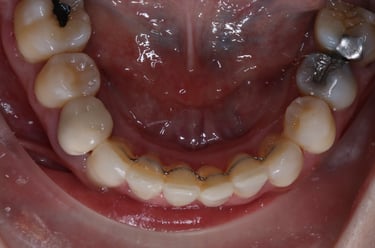

Before & After photos

before

after

Case Example =full set of photos